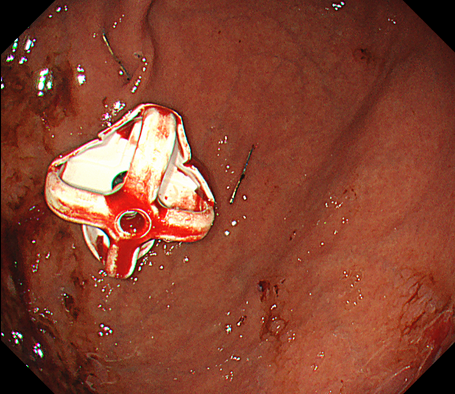

内視鏡下ステント留置術

消化管の狭くなっている部分に対してステント(筒のようなもの)を挿入し狭窄部を広げる治療になります。

主に癌などの悪性腫瘍の狭窄に対して行う治療で、切除不能狭窄の症状緩和目的や腸閉塞症状を伴う狭窄の緊急手術回避目的で行います。